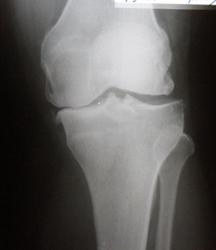

суставная щель неровномерно сужена только с одной стороны.заострение и вытягивание межмыщелкового возвыщение.подхрящевая костная пластинка уплотнена.костные разрастание по краям суставной поверности.

Краевые костные разрастания и субхондральный остеосклероз всегда являются косвенными признаками функциональной несостоятельности

суставных хрящей.

Обязательными признаками деформирующего артроза являются сужение суставной

щели, краевые костные разрастания, субхондральный остеосклероз. Второй и третий признаки (краевые костные разрастания и субхондральный остеосклероз) могут широко варьировать, но без первого признака (сужение суставной щели) деформирующего

артроза не бывает. Не всякая деформация суставных концов является деформирую- щим артрозом.

В результате проведенного рентгенологического исследования сустава выявлены:

1. Признаки прямо указывающие на дегенерацию суставного хряща:

- сужение рентгеновской суставной щели соответствует объемному уменьшению суставного хряща;

- субхондральный остеосклероз, как ответная реакция костной ткани на увеличение механической нагрузки в суставе;

- остеофиты на краях суставных поверхностей, как ответная реакция костной ткани на увеличение механической нагрузки в суставе.

Диагностическое заключение.

Деформирующий артроз сустава стадии по трёхстепенной классификации по Н.С. Коссинской; стадии по классификации Kellgren и Lawrence.